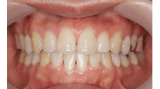

■症例1

Before

After